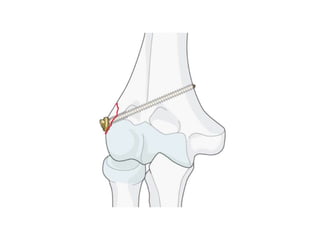

ORIF with lateral column approach

• Indications

– isolated capitellar fractures

– type IV fractures that can have trochlear

involvement

• Approach

– lateral approach recommended for isolated Type I

and Type IV fx

• Technique

– Headless screw fixation

– Avoid disruption of the blood supply that comes

from the posterolateral aspect of the elbow

– Do not destabilize LUCL